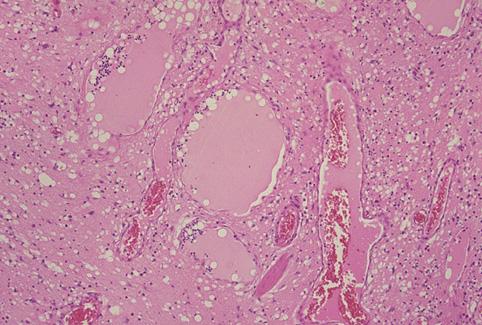

질환(병리주체)의 분류 종양양 병변/염증성 유섬유 용종(IFP)

부위(장기별) 위(부위)/분문

검사방법 마이크로

종양의 최대경(밀리미터) 35~40